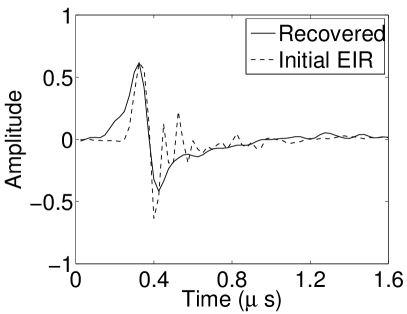

In Figure 17, the results corresponding to use of the 3D imaging model that incorporated SIR effects are shown. The EIR estimated by the VP algorithm is also shown. In Figure 18, images and EIRs reconstructed by use of the VP algorithm with different regularization parameters values are shown.

Similar to the case described above where the transducer SIR was neglected, these results reveal that use of the VP algorithm can produce images with a cleaner background and enhanced spatial resolution than yielded by use of a conventional iterative algorithm that employed the measured EIR. For example, detailed information regarding the vessels near the organ’s periphery was better preserved by the VP algorithm than by the conventional iterative algorithm. These images corroborate our assertion that the VP algorithm can significantly reduce the artifacts and distortions in the reconstructed image. It is also worth pointing out that, unlike the numerical phantom studies, the artifacts and distortions in the images may be caused not only by the inaccurate EIR but also by other factors, such as neglecting acoustic heterogeneities and the variation of the EIRs among the elements of the transducer array. In such cases, the EIR estimated by the VP algorithm represents an effective system impulse response that minimizes the inconsistency between the measured data and the imaging model.

VI-F Auto-focus capabilities

Conventional PACT reconstruction algorithms assume that the medium is described by a constant speed-of-sound (SOS) value. In practice, this value may not be known precisely and can be tuned [TVZL2011] to maximize the spatial resolution of the reconstructed images. The effect of an incorrect SOS value can sometimes be compensated for by use of the VP algorithm due to modification of the EIR during the joint estimation. Figures 19(a) and 19(b) show images reconstructed by use of the conventional iterative method and the VP algorithm, respectively, when different constant SOS values are assumed. The 2D imaging model that ignored the SIR was employed. Nearly identical images were reconstructed by use of the VP algorithm, even though the assumed SOS values were different in each case. The images contained reduced artifact levels as compared to those reconstructed by use of the conventional method. The recovered EIRs differed by a time shift (as displayed in Fig. 19(c)). Since the object was located near the center of the transducer array and was small compared to the radius of the array, the scaling effect due to the inaccurate SOS can be approximated by the shift of the EIR, which explains how the recovered EIR compensates for the error in SOS value.